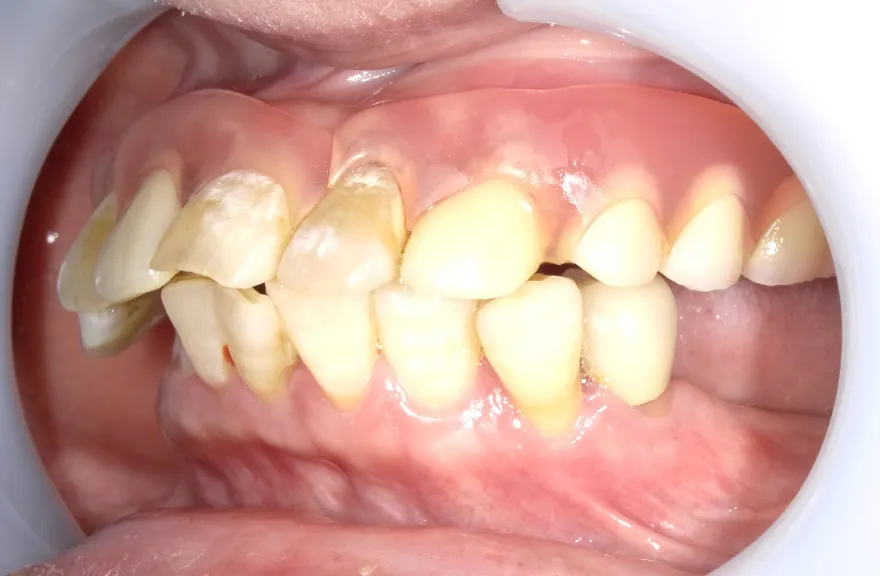

【治療例 3】奥歯が痛い、全体的にみて欲しい 60歳

- 相談内容

-

今まで何回歯を入れてもトラブルが起きるために、奥の歯を入れないまま今日に至る、ということでした。

噛み合わせ・骨格を読み解き、今後の人生でトラブルが起きにくいように全体的な治療計画を練りました。 - 治療費用・方針

骨格の前後的な差がある方でした。術前のレントゲンより、上下で歯牙の損傷に明らかな差があるのがみてとれます。

上の歯がないところにインプラント治療を行い、上顎は全てインプラントフィクスチャーによる固定性の歯を入れられることも費用的には可能な方でした。

しかし、治療において重要なのは今目の前の歯を見ることではなく、なぜ目の前の歯になったかを考え、未来へ活かすことです。

骨格的な前後差を考慮することなく歯をいれても、装着した人工物は決して長持ちしません。

今回の症例では、敢えて上顎は総義歯形態をとり、骨格的な前後の差を解消するよう工夫しました。

上顎の残っていた歯も、差し歯としては使えずとも、敢えて根だけ残すことによって組織を温存し、義歯の安定に寄与するよう設計しました。

ここまで全体的にしっかり治療しておけば、今後の人生においてトラブルになるようなことにはならないでしょう。 - 治療のリスク